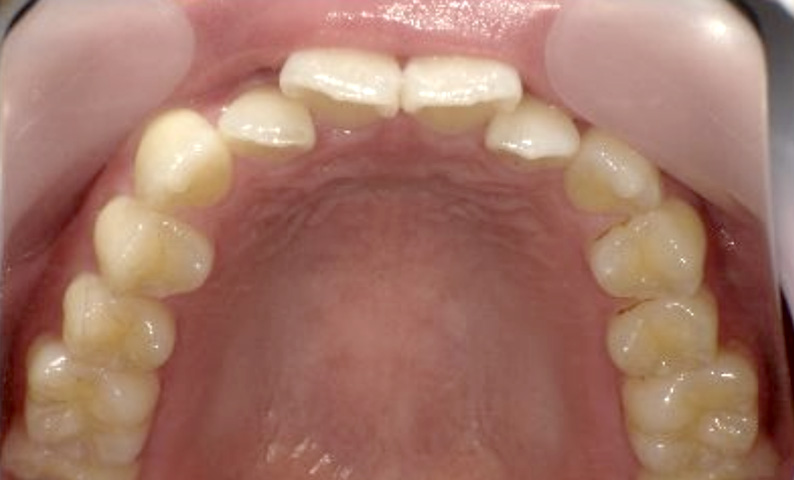

症例_024 上下顎の部分矯正

治療期間:13ヶ月金額:51万円+税女性前歯のガタガタ八重歯

| Before | After |

|---|---|

|